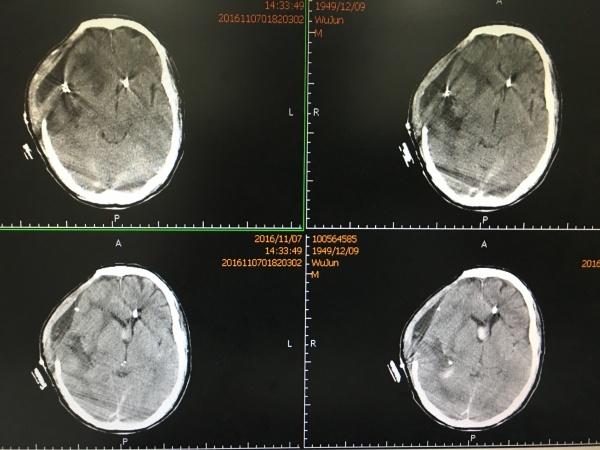

片中示巨大脑内血肿,而且出血破入脑室,右侧侧脑室铸型。

我们急诊在全麻下行开颅血肿清除+动脉瘤夹闭+颅内压监护探头植入术,术后复查头颅CT如下: